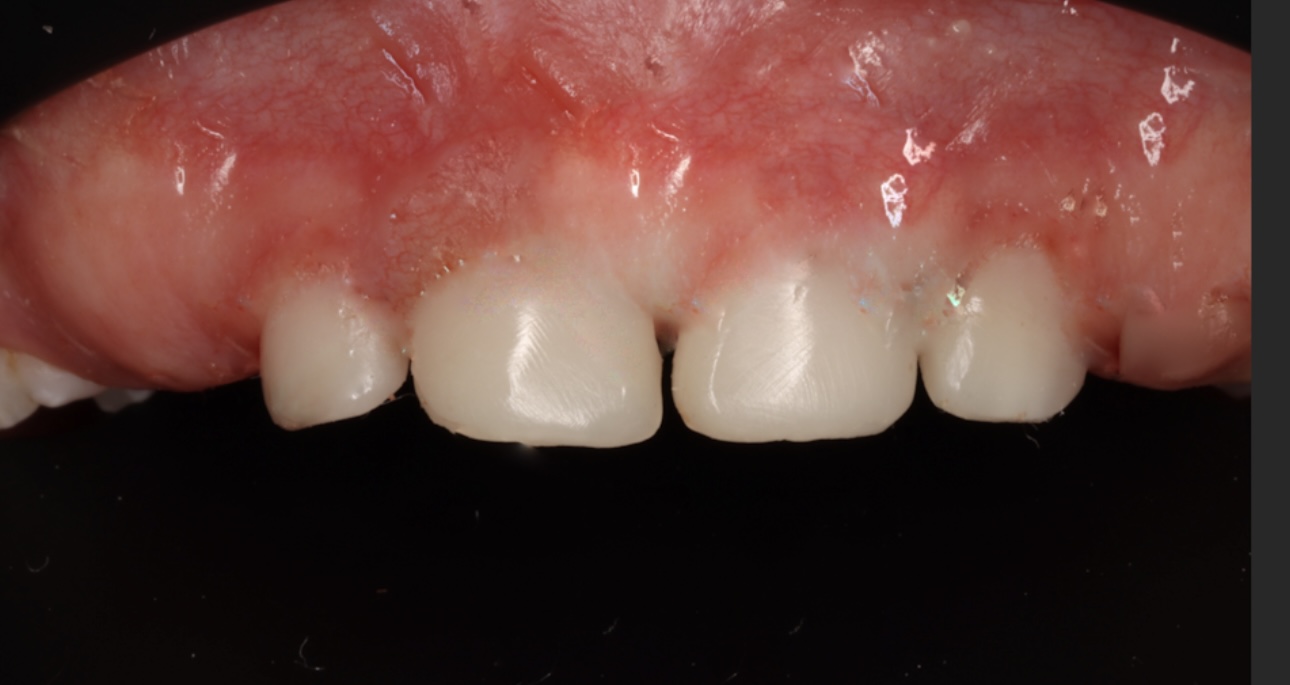

Кейін

Кейін

Кейін

Кейін

Кейін

Кейін